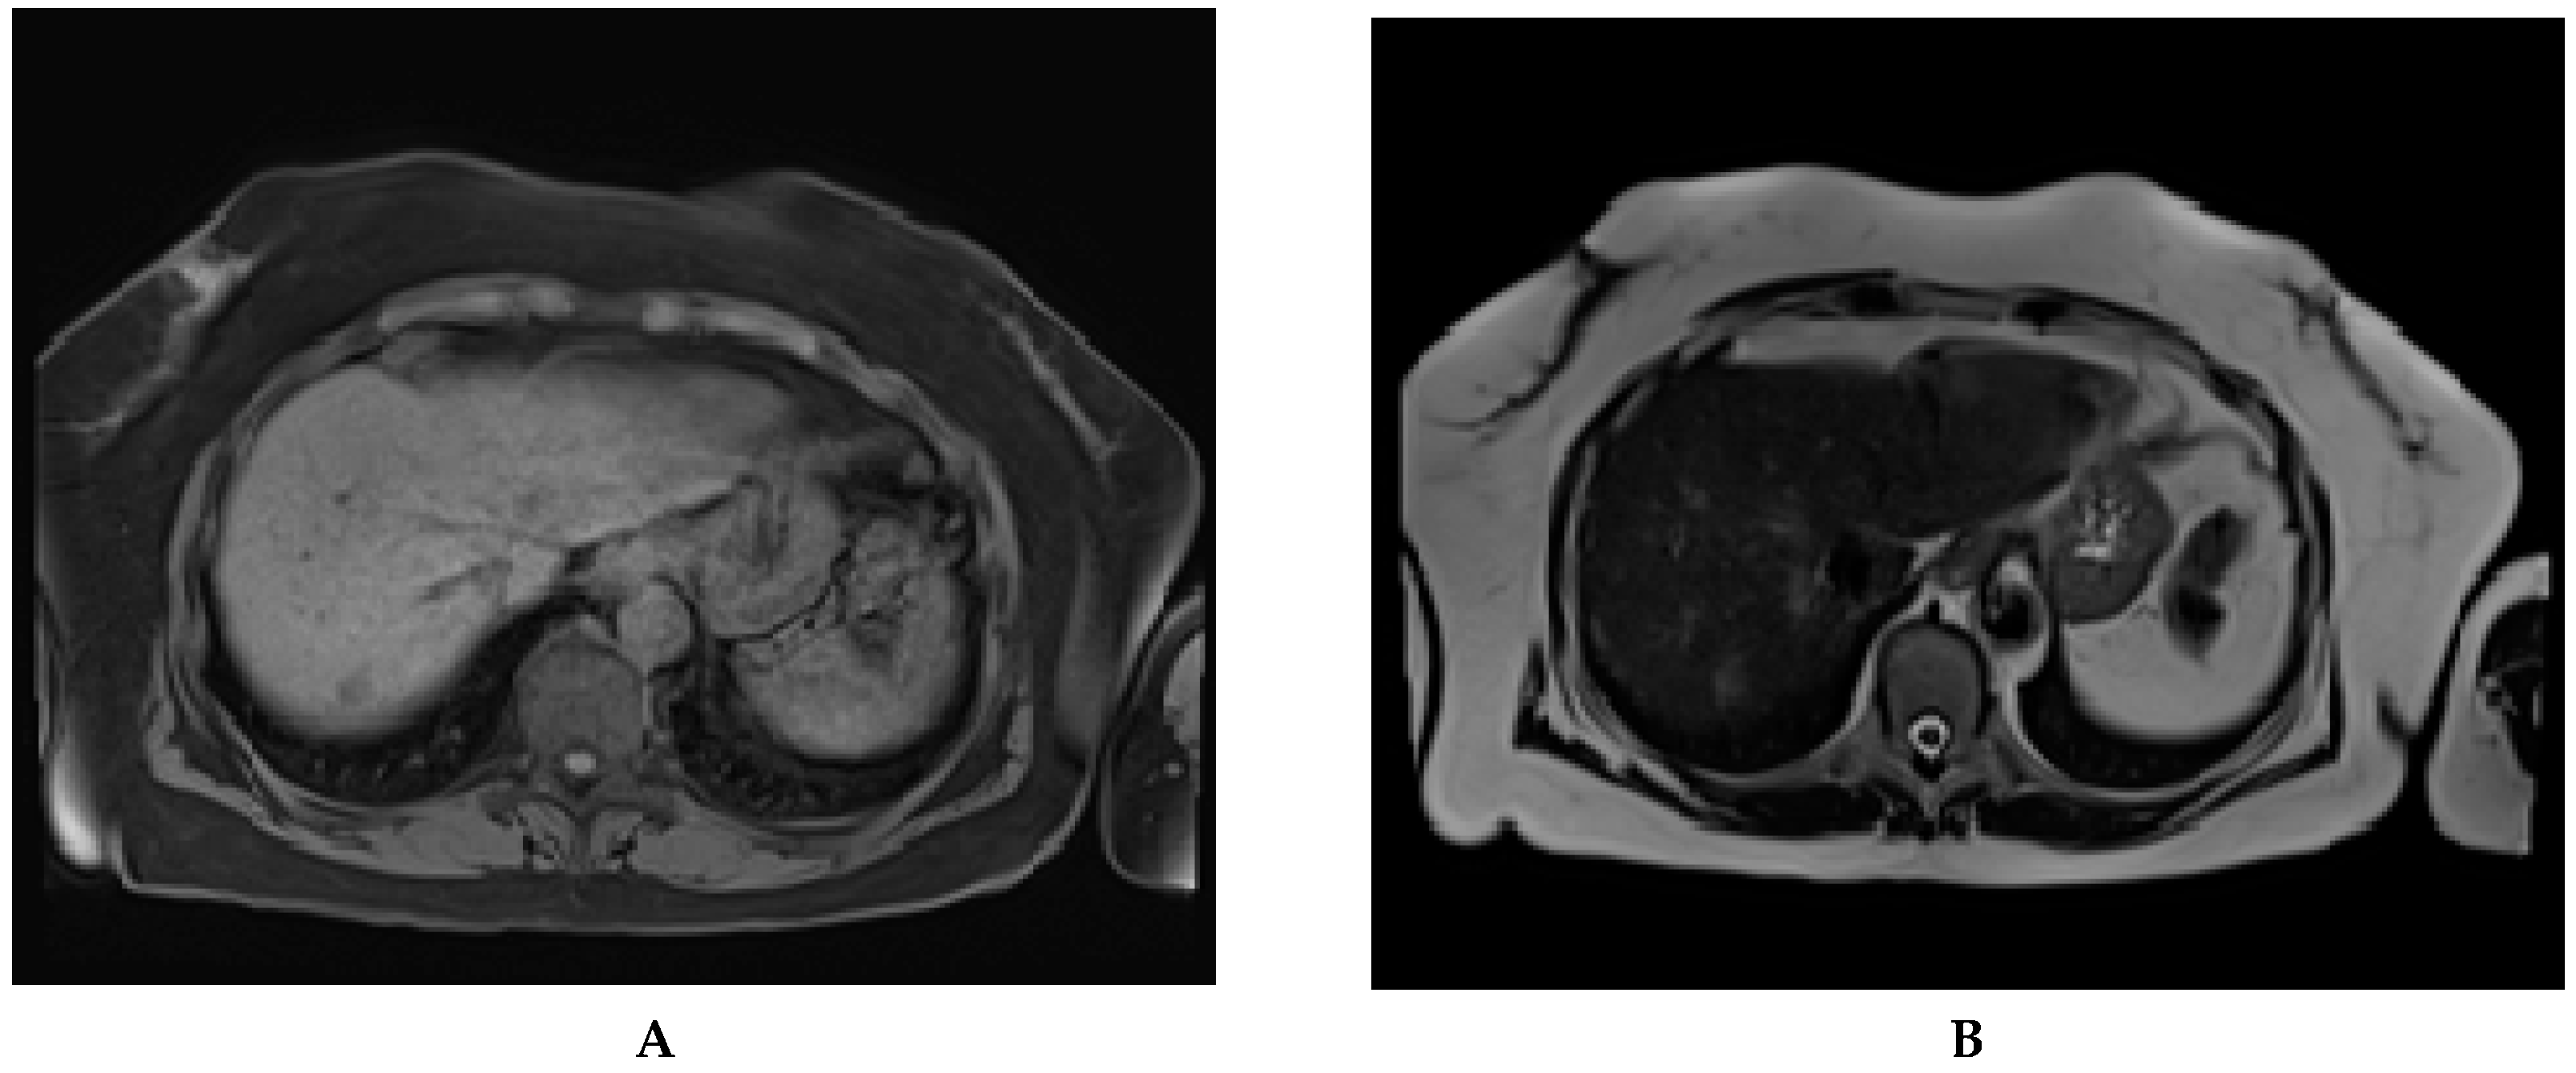

| Study | Year | Technique | Sensitivity | Specificity |

|---|---|---|---|---|

| Kim, et al. [95] | 2014 | Non-contrast MRI | 91% | 77% |

| Pocha, et al. [87] | 2013 | Contrast-enhanced CT | 87% | 87% |

| Van Thiel, et al. [88] | 2004 | Contrast-enhanced CT | 70% | 100% |

| Kim, et al. [54] | 2017 | Liver-specific contrast-enhanced MRI | 83% | Not available |

| Yu, et al. [90] | 2011 | Contrast-enhanced CT | 65% | 96% |

| Yu, et al. [90] | 2011 | Contrast-enhanced MRI | 72% | 87% |

| Chan, et al. [93] | 2019 | Non-contrast, abbreviated MRI | 85% | 93% |

| Besa, et al. [96] | 2017 | Contrast-enhanced abbreviated MRI | 80% | 87% |